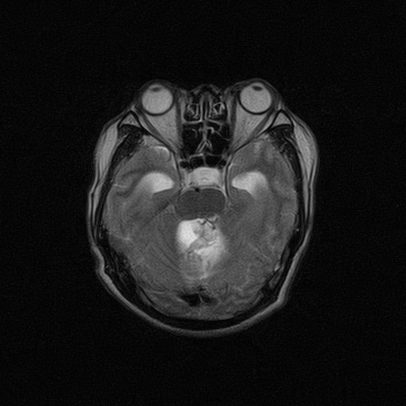

标题: MRI2064:少见病例。男性52,视力下降多年。 [打印本页]

标题: MRI2064:少见病例。男性52,视力下降多年。

四脑室区见混杂信号占位影,脑室系统扩张明显,临近结构显著受压称位,患者52岁,多考虑室管膜瘤可能性大

考虑第四脑室室管膜瘤并阻塞性脑积水。

定位;脑室内富血供占位

1,脑室内血管母细胞瘤。

应该是来源于小脑蚓部的占位,如血管母细瘤或星形细胞瘤

小脑血管母细胞瘤.并外压性脑积水.

比较典型的脉络丛乳头状瘤并脑积水,鉴别小脑蚓部血管母细胞瘤。